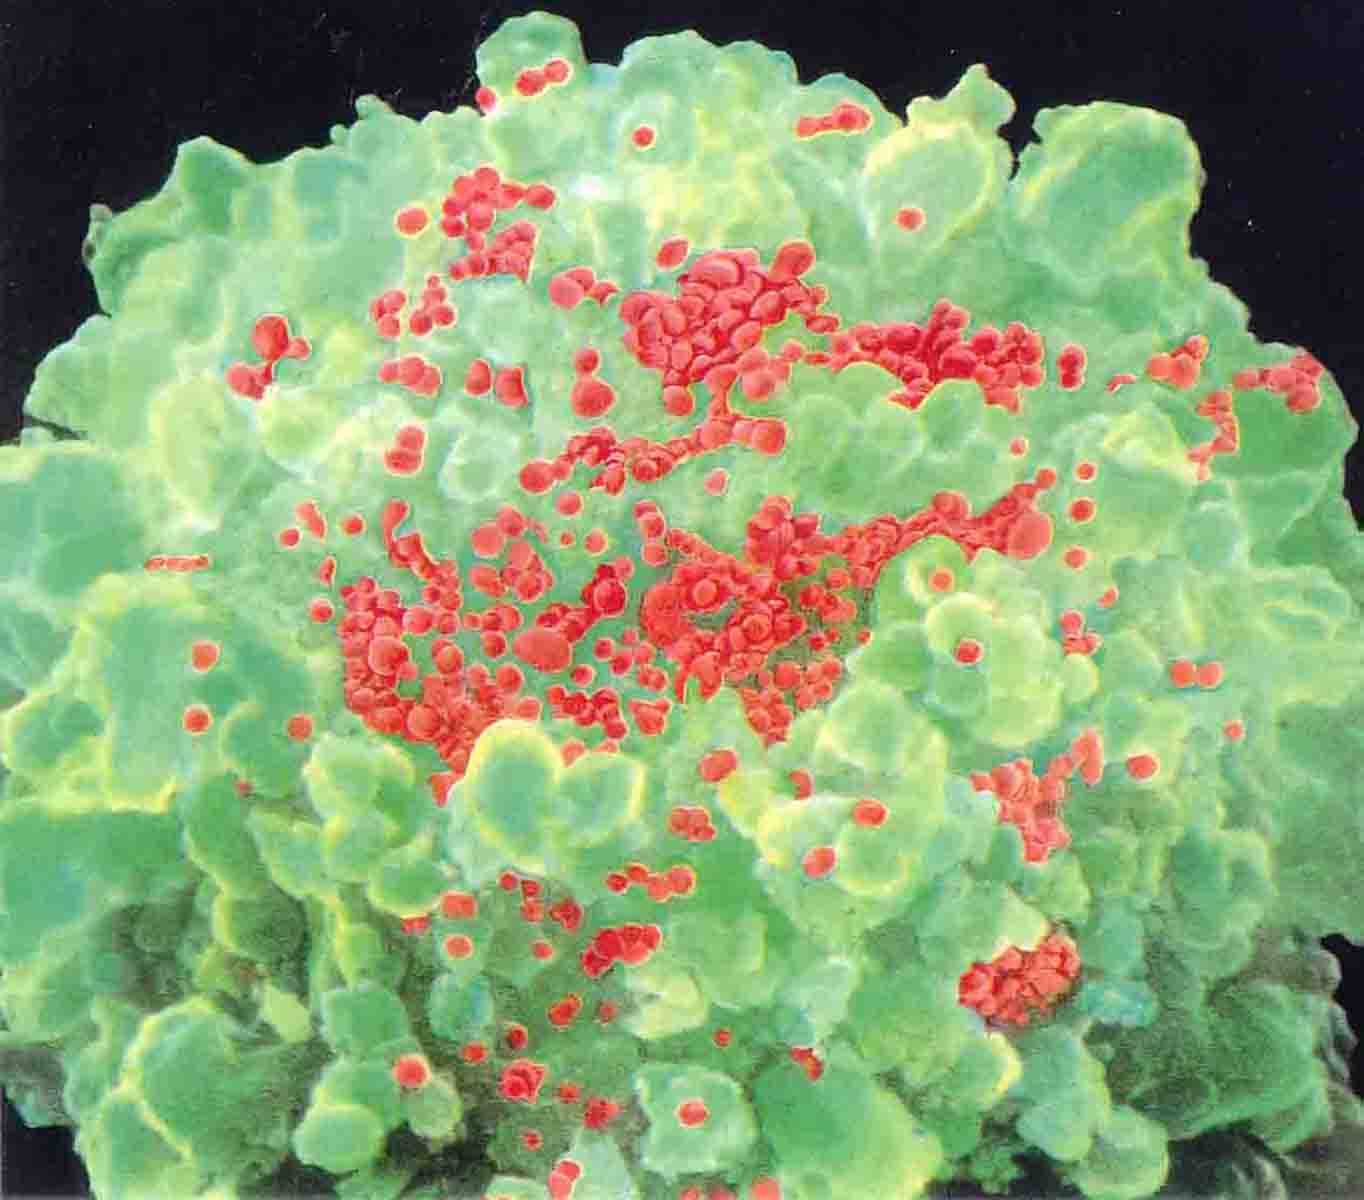

Aids, Depictions of Aids through Art

Aids, Depictions of Aids through Art |

Aids, Εικαστικοί καλλιτέχνες δημιουργούν